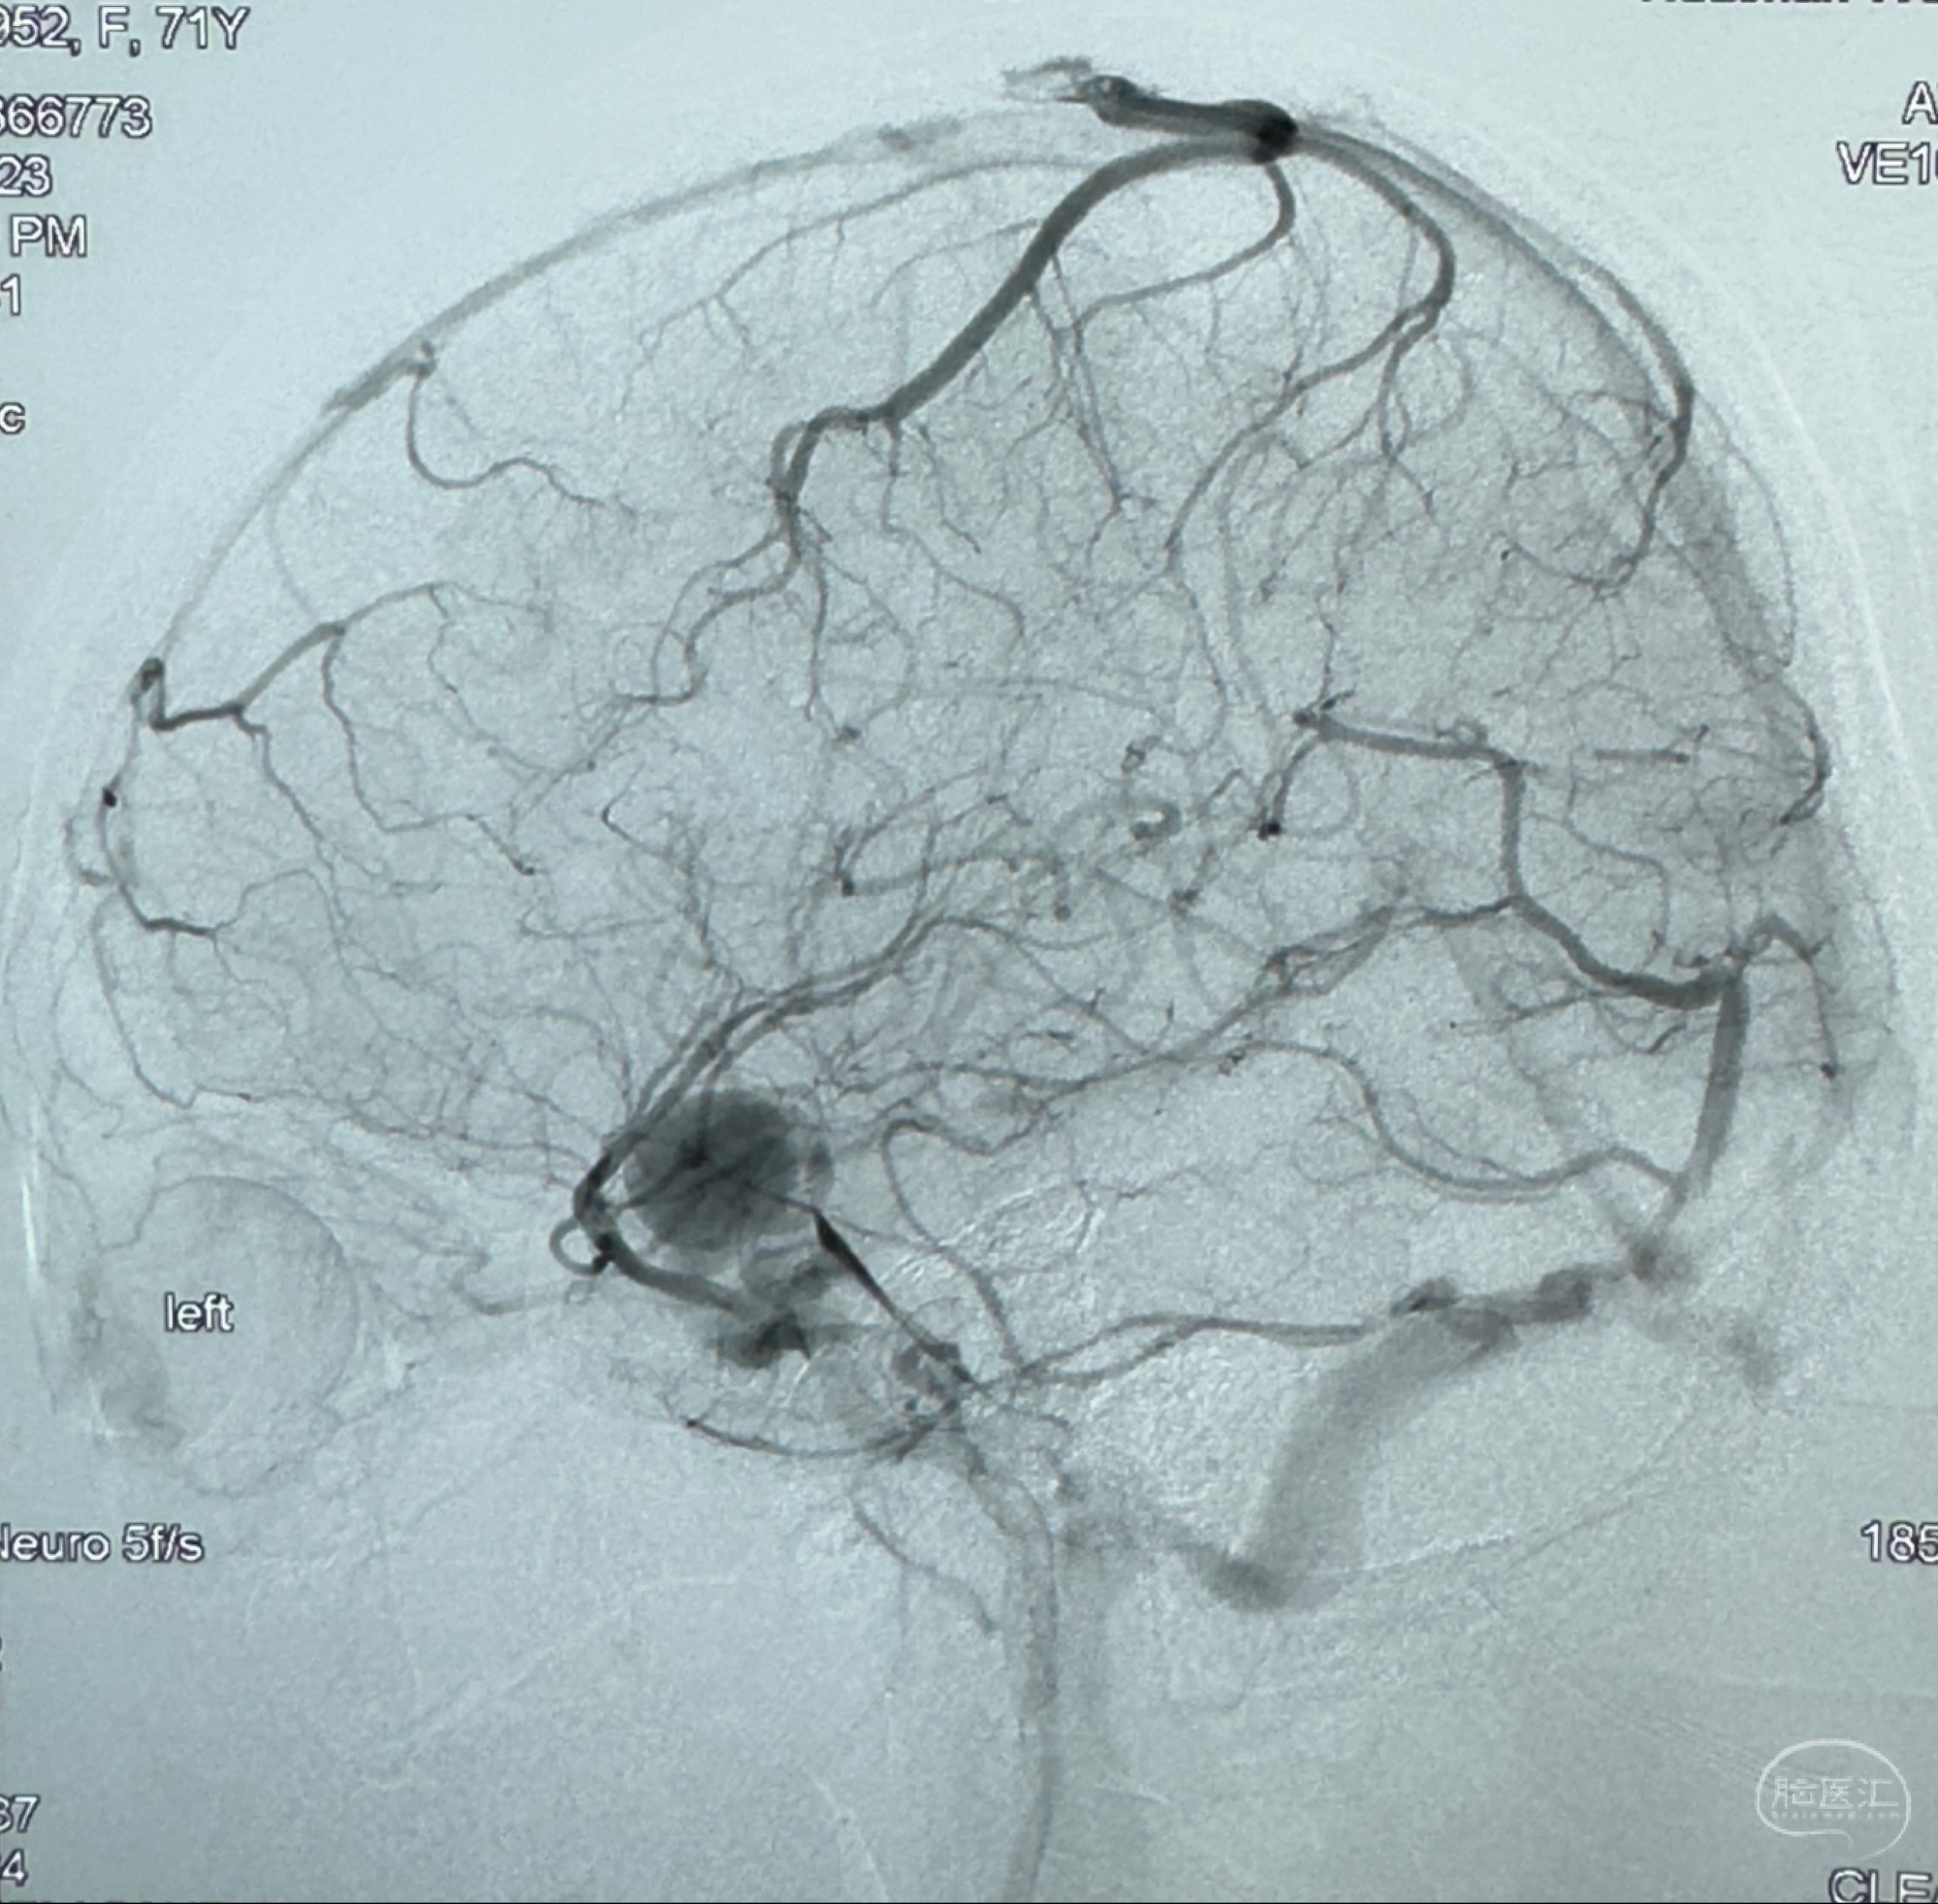

2023-12-08外院DSA:右侧颈眼动脉瘤,约13*12mm大小,压颈试验显示左右向及后向前代偿可

2023-12-18全麻下行DSA➕密网支架植入备弹簧圈辅助栓塞

旋转3D展示动脉瘤局部的血管构筑

测量动脉瘤的大小:16*13.8*7.6mm大小,较原先变大,考虑双抗后瘤内血栓溶解可能

观察动脉瘤腔内的血流动力学情况